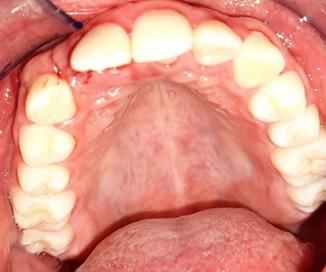

Endodoncia y rehabilitación protésica como alternativa terapéutica de geminación dental

Tomando en cuenta nuestro caso clínico, los estudios histopatológicos determinaron que estamos frente a un proceso inflamatorio crónico inespecífico con fibrosis marcada, su extirpación fue exitosa sin ningún tipo de complicaciones dentro de la cirugía y del postoperatorio; Zambuzzi et al reportaron en un estudio que la hidroxiapatita natural de hueso bovino promueve un ambiente adecuado para la adhesión, proliferación y diferenciación de osteoblastos, lo cual lleva a una adecuada resolución del hueso (3); desde otro ángulo Chiapasco A. et al comparan la regeneración de cavidades quísticas mediante esponjas de colágeno (mantenedoras del espacio y estabilizadoras) y hueso liofilizado desmineralizado de cadáver; no encontraron diferencias estadísticamente significativas entre ambos grupos a los dos años, lo que confirma que en cualquier caso se presentará buena cicatrización ósea posterior a la quistectomías, al utilizar materiales aloplásticos, injertos o la propia formación ósea espontánea; ambos procedimiento utilizados en nuestro paciente (4).

RIIS UNIVALLE. Jul-Dic. 17(43), 2022; ISSN: 2075-6208 105 Aplicación de biomateriales post exeresis en un quiste inflamatorio radicular Adrián-Hurtado y cols.

Figura 9. Obtención del Sticky bone (SB), mezcla del A- PRF más el hueso bovino.

Hernández R. et al concuerdan con que el uso de injertos óseos es un método seguro, simple, eficaz y que además el odontólogo puede emplear para diversos defectos óseos alveolares, siempre y cuando sea considerado su sitio de colocación ya que esto influye directamente con el éxito del tratamiento. En sus tres reportes de casos pudo evidenciar que el uso de injertos promovió su buena oseointegración y presentó un alto nivel de biocompatibilidad, además ninguno de estos tres autores difiere en sus opiniones (5) (9) (10).

Cuando existe pérdida de tejido óseo extenso es importante utilizar biomateriales que produzcan osteoconducción, osteoinducción y osteogénesis, puesto que estos tienen la capacidad de estimular

REFERENCIAS BIBLIOGRÁFICAS

la formación ósea de una manera más rápida; dependiendo del tipo de material veremos que la formación ósea será más adecuada, tanto en volumen como en calidad; con esto no tratamos de indicar que la recuperación fisiológica no será buena, sino que esta tarda más tiempo, en contraste con el uso biomateriales y el aumento de densidad ósea; debido a la extensión de la cavidad, el relleno de la misma con el Sticky bone y cubrir con una membrana de pericardio porcino, se espera que cumplan la función osteoconductora en la cavidad. Basándonos en los estudios y revisiones recientes, esperamos buenos resultados en nuestros pacientes, debido a que el tiempo de neoformación dura aproximadamente 6 a 8 meses, por lo cual aún se encuentra en proceso.

1. García, A., Buljadón, A., & Rodríguez, A. (Febrero de 2015). Lesiones periapicales. Diagnóstico y Tratamiento. Avances en Odontoestomatología, XXXI(1), 31-42. Recuperado el 9 de Juio de 2018, Doi: https://doi.org/10.4321/S0213-12852015000100005

2. Swennen G, Dempf R, Schliephake H. Cranio-facial distraction osteogenesis: a review of the literature. Part II: Experimental studies. Int J Oral Maxillofac Surg. 2002 Apr; 31(2): 123-35. doi: https://doi.org/10.1054/ijom.2002.0225

3. Rebolledo M, Harris J, Higgins E, Molinares L. Cicatrización y regeneración ósea de los maxilares después de una quistectomía: reporte de un caso y revisión de la literatura. Univ Odontol. 2011 Jul-Dic; 30(65): 71-78 Recibido para publicación: 15-05-2011 Correcciones recibidas: 09-09-2011 Aceptado para publicación: 11-10-2011 Disponible en http://www.javeriana.edu.co/

4. Zambuzzi WF, Ferreira CV, Granjeiro JM, Aoyama H. Biological behavior of pre-osteoblasts on natural hydroxyapatite: a study of signaling molecules from attachment to differentiation. J Biomed Mater Res. 2011 May; 97(2): 193-200. Epub 2011 Mar 10. Doi.10.1002/jbm.a.32933 https://doi. org/10.1002/jbm.a.32933

5. Chiapasco M, RossiA, Motta JJ, Crescentini M. Spontaneous bone regeneration after enucleation of large mandibular cysts: a radiographic computed analysis of 27 consecutive cases. J Oral Maxillofac Surg. 2000 Sep; 58 (9): 942-8. Discussion 949. Doi https://doi.org/10.1053/joms.2000.8732

6. Edgar Eduardo Serrano Mejía Trabajo de grado para otorgar el título de Odontólogo Director Nohora Camila Rúgeles Páez Esp. Implantología oral y reconstructiva Universidad Santo Tomás, Bucaramanga División de Ciencias de la Salud Faculta de Odontología 2020. http://hdl.handle. net/11634/20496

7. Block MS. The processing of xenografts will result in different clinical responses. Journal of Oral and Maxillofacial Surgery 2018. Doi. 10.1016/j.joms.2018.10.004

8. Johnson, B., Fayad, M., & Witherspoon, D. (2011). Cirugía Perirradicular. En K. Hargreaves, & S. Cohen, Vías de la pulpa (págs. 720-755). Barcelona, España: Elsevier Mosby. Doi. https://doi. org/10.1016/B978-0-323-06489-7.00021-7

9. Morales, D., & Vila, D. (2016). Regeneración ósea guiada en Estomatología. Revista Cubana de Estomatología, LIII(1), 67-83. Recuperado el 17 de Julio de 2018, de http://scielo.sld.cu/scielo. php?script=sci_arttext&pid=S0034-75072016000100008

10. Rebolledo, M., Harris, J., Higgins, E., & Molinares, L. (2011). Cicatrización y regeneración ósea de los maxilares después de una quistectomía: reporte de caso y revisión de la literatura. Universitas Odontológica, 30(65), 71-78. Obtenido de http://www.javeriana.edu.co/universitasodontologica

RIIS UNIVALLE. Jul-Dic. 17(43), 2022; ISSN: 2075-6208 106 Aplicación de biomateriales post exeresis en un quiste inflamatorio radicular Adrián-Hurtado y cols.

DOI: https://doi.org/10.52428/20756208.v17i43.390

Inclusión dentaria por un odontoma compuesto

Dental inclusion by a compound odontoma

Javier Adrian Burgos 1. Francis Daniela Argandoña Ortiz2. Gabriela Adriana Lara León3

1Medico cirujano, Cirujano Dentista, Esp. En Cirugía Bucal, Msc. En Implantología Oral, Docente Univalle Sub- Sede La Paz jadrianb@univalle.edu

2 Estudiante de la Carrera de Odontología, Universidad Privada del Valle La Paz, aof2015031@est.univalle.edu

3 3Estudiante de la Carrera de Odontología, Universidad Privada del Valle La Paz. Llg2016973@univalle.edu

Recibido:27/10/2022

Revisado:08/11/2022

Aceptado:05/12/2022

Cita: Adrián Burgos, J. B., Argandoña Ortiz, F. D., & Lara León, G. A. Inclusión dentaria por un odontoma compuesto. Revista De Investigación E Información En Salud UNIVALLE 2022; 17(43): p.107-115 https:// doi.org/10.52428/20756208.v17i43.390

Correspondencia: Dr. Javier Boris Adrián Burgos, La Paz, Bolivia, jadrianb@univalle.edu

Nota: Los autores declaran no tener conflicto de intereses con respecto a esta publicación y se responsabilizan del contenido vertido, teniendo acuerdo informado del paciente y sus familiares. Todos los autores participaron activamente en la realización del artículo, que además fue autofinanciado.

RESUMEN

Se considera que los odontomas son tumores benignos, mixtos, asintomáticos y de crecimiento lento. Son una lesión hamartomatosa, de origen odontogénico formado por células epiteliales y mesenquimales. Según la clasificación de la Organización mundial de la salud (OMS) 2022 los odontomas son tumores benignos mixtos, existen 2 tipos de odontomas, el compuesto y el complejo. La etiología de esta lesión es desconocida pero asociada a traumatismos durante la dentición primaria, mutaciones genéticas y herencia.

El presente caso clínico se realizó en la Clínica Odontológica UNIVALLE Sub-sede La Paz, Bolivia, con un procedimiento quirúrgico, reportando un caso clínico de un paciente de sexo masculino de 15 años de edad con ausencia de pieza 1.2, se realizaron estudios complementarios como radiografías y tomografías previo al tratamiento quirúrgico, al examen imagenológico se observa una masa radiopaca coincidente con una imagen de odontoma compuesto, dado al diagnóstico acertado se planifica el tratamiento quirúrgico con anestesia local para la exeresis del mismo, con buen resultado.

Palabras clave: Dentículos, incisivo lateral incluido, odontoma compuesto.

RIIS UNIVALLE. Jul-Dic. 17(43), 2022; ISSN: 2075-6208 107 Reporte de caso Case Report REVISTA DE INVESTIGACIÓN E INFORMACIÓN EN SALUD RIIS UNIVALLE. Jul-Dic .2022; ISSN: 2075-6208 revistas.riis@revistas.univalle.edu Derechos de autor 2022 Javier Adrian Burgos, Francis Daniela Argandoña Ortiz, Gabriela Adriana Lara León. Esta obra está bajo licencia internacional Creative Commons Reconocimiento 4.0

ABSTRACT

Odontomas are considered to be benign, mixed, asymptomatic and slow-growing tumors. They are a hamartomatous lesion of odontogenic origin formed by epithelial and mesenchymal cells. According to the World Health Organization (WHO) 2022 classification, odontomas are mixed benign tumors, there are 2 types of odontomas, compound and complex. The etiology of this lesion is unknown but it is associated with trauma during the primary dentition, genetic mutations and heredity.

The present clinical case was carried out at the UNIVALLE Dental Clinic Sub-headquarters La Paz-Bolivia, with a surgical procedure, reporting a clinical case of a 15-year-old male patient with the absence of tooth 1.2, complementary studies were carried out such as X-rays and CT scans prior to surgical treatment, the imaging examination revealed a radiopaque mass coinciding with an image of a compound odontoma, given the correct diagnosis, surgical treatment with local anesthesia was planned for exeresis, with good results.

Key words: Compound odontoma, denticles, lateral incisor included.

INTRODUCCIÓN

Los tumores odontogénicos más comunes son los odontomas; el término odontoma fue introducido en 1867 por Broca; con la característica de ser un hamartoma benigno mixto de origen dentario, es decir, es una lesión de células odontogénicas epiteliales y mesenquimatosas (1). La etiología exacta de los odontomas aún no se conoce con exactitud, sin embargo, algunos autores atribuyen su origen con algunas teorías, como la de los restos paradentarios de Malassez y la teoría de Rywkind, además existe una posible relación con traumatismos dentoalveolares en la dentición primaria, procesos infecciosos, hiperactividad odontoblástica y a síndromes hereditarios como es el síndrome de Gardner (2); según la última clasificación de la Organización Mundial de la Salud (OMS) de lesiones Odontogénicas de la 5ta edición del 2022, indica que los odontomas son considerados tumores odontogénicos benignos, mixtos (epiteliales y mesenquimatosos), estos pueden ser compuestos y complejos (3).

Los odontomas son los tumores odontogénicos con mayor frecuencia de aparición y representan 51 % de estas lesiones; existe mayor predominio en niños y adolescentes, observándose poca diferencia en su incidencia entre mujeres y varones; tiene una frecuencia de aparición de 22 % en la mandíbula y de 67 % en el maxilar (1); los odontomas suelen ser clínicamente asintomáticos, de crecimiento limitado, producen retención dentaria y su hallazgo es casual en revisiones radiográficas rutinarias;

cuando presentan alguna sintomatología, los signos clínicos más frecuentes son el retraso en la erupción dental y la tumefacción a nivel del proceso alveolar afectado (4). También pueden estar relacionados con dientes supernumerarios, impactados, retenidos, inflamación e infección (5). La frecuencia mundial de los tumores odontogénicos varía de 1 % al 32 %, reportándose el odontoma como la lesión más prevalente entre el 35 al 75 %, siendo más común el odontoma compuesto (6).

El odontoma compuesto es una malformación en la que están representados todos los tejidos dentarios con un patrón más ordenado, en forma de dentículos, se sitúan comúnmente en el área de incisivos y caninos del maxilar superior, con menos frecuencia en las zonas anteroinferior y posteroinferior; los odontomas complejos contienen todos los tejidos dentarios de manera desorganizada, en forma de una masa nudosa solida; tienen mayor predilección por las zonas de segundos y terceros molares inferiores (1) (6). Radiográficamente el odontoma compuesto se presenta como una imagen mixta (radiopaca y radiolúcida), que adopta una configuración similar a dientes (dentículos), rodeados por un halo radiolúcido (5). Estas lesiones pueden ser detectadas con una radiografía panorámica pero no brindan la suficiente información para la planeación del abordaje y procedimiento; la tomografía axial computarizada es el mejor método de evaluación para este tipo de lesiones, brindan más información que la radiografía panorámica, muestra imágenes en tres dimensiones, tiene baja dosis de radiación, imágenes en tiempo corto y mejor resolución (7).

RIIS UNIVALLE. Jul-Dic. 17(43), 2022; ISSN: 2075-6208 108

Inclusión dentaria por un odontoma compuesto Burgos-Argandoña-Lara

Debido a su bajo potencial de crecimiento y la recidiva infrecuente, el tratamiento es quirúrgico, llevando a cabo una enucleación y debe practicarse con sumo cuidado para no lesionar los dientes que no han hecho erupción, tratando de conservar el diente permanente, el cual requerirá tratamiento ortodóntico quirúrgico (8).

PRESENTACION DEL CASO CLÍNICO

Acude a la clínica odontológica UNIVALLE Sub sede La Paz, paciente de sexo masculino de 15 años de edad, con mal posición dentaria en el sectante anterosuperior derecho, previamente habido tratamiento quirúrgico (exeresis) de pieza 5,2 y evidenciando radiográficamente una masa tumoral radiopaca (Figura 1).

Figura 1. Radiografía periapical previa a la extracción de la pieza temporaria 5.2. Se observa por primera vez una imagen mixta radiopaca-radiolucida circunscrita presuntiva de un odontoma y la presencia de la pieza permanente 1.2 incluida.

En el momento del examen clínico intraoral se observa la erupción de gran parte de todas las piezas permanentes exceptuando la pieza 1.2 en el cual existe un espacio edéntulo. Viendo minuciosamente

se encuentra una ligera prominencia por vestibular donde no presenta signos de inflamación ni dolor a la palpación, sin encontrar características relevantes en la mucosa adyacente (Figura 2). Inclusión

RIIS UNIVALLE. Jul-Dic. 17(43), 2022; ISSN: 2075-6208 109

dentaria por un odontoma compuesto Burgos-Argandoña-Lara

Posterior al examen clínico intra y extraoral se solicitó estudios complementarios como radiografías